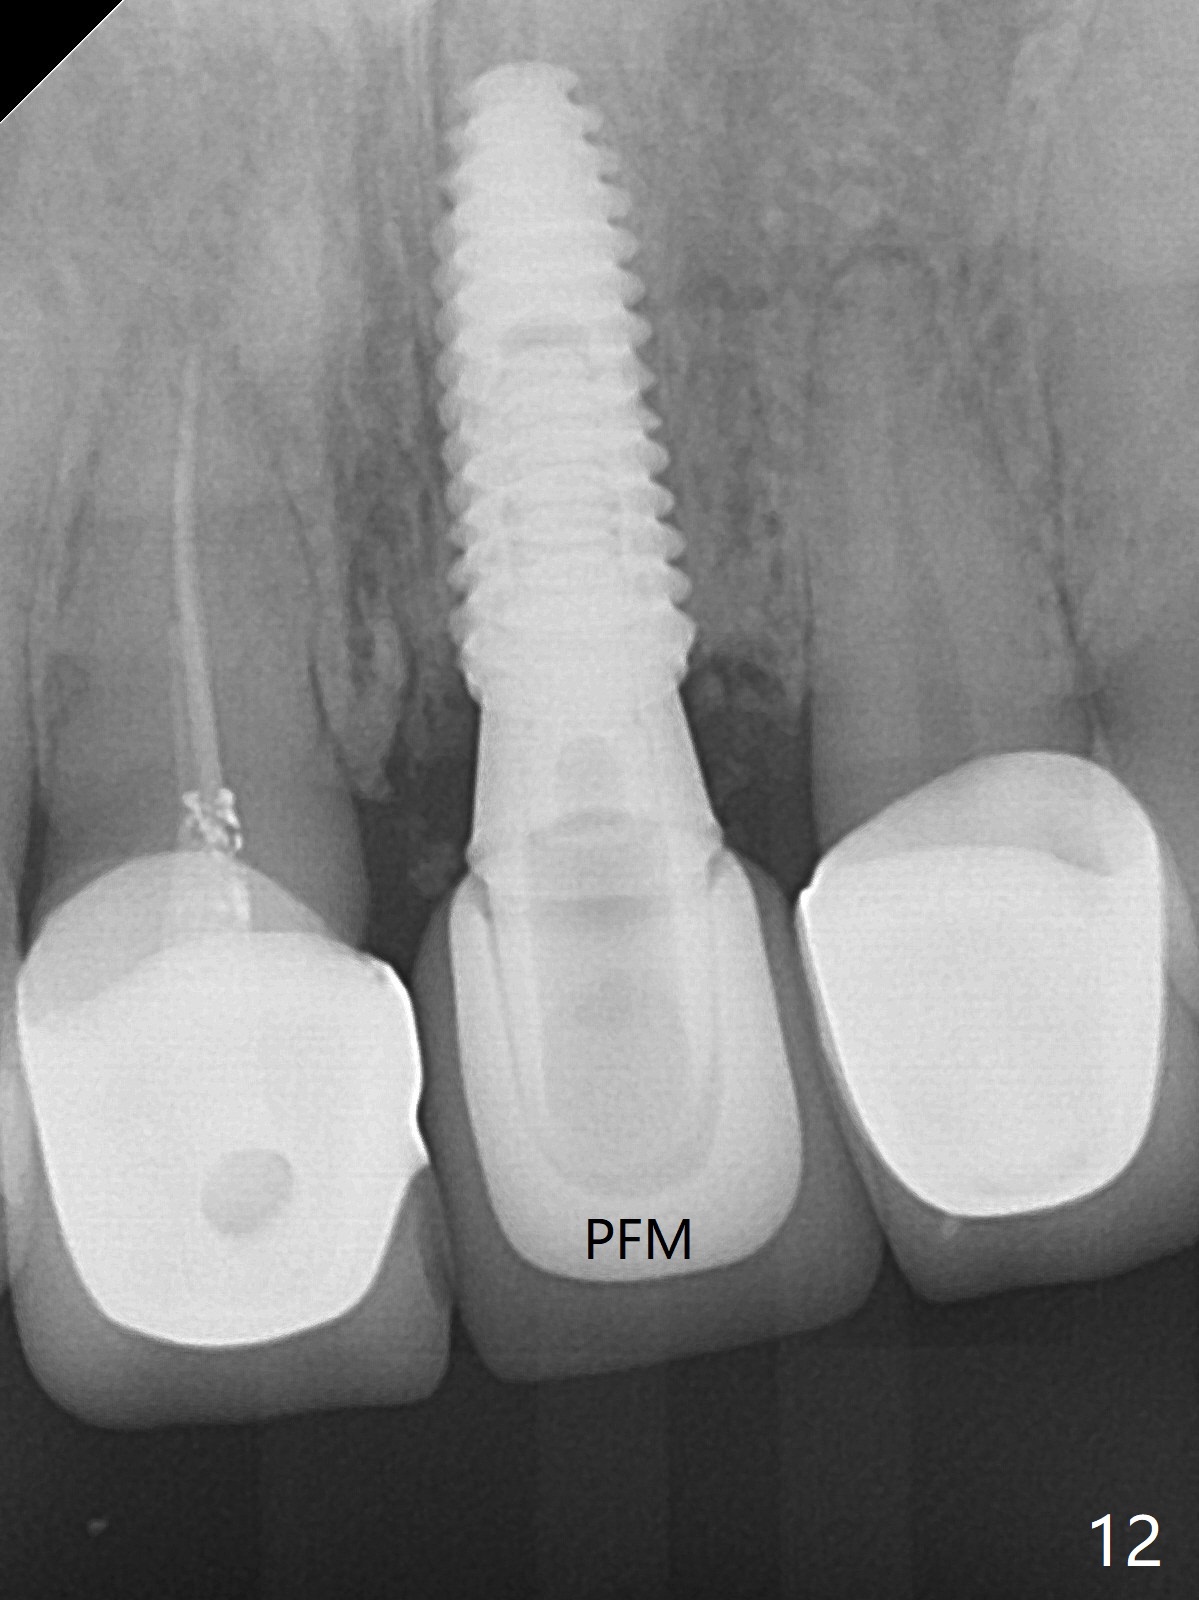

After sectioning the splinted crowns at #8 and 9 (Fig.1,2 (*: open bite)), the tooth #9 is deemed nonsalvageable because of caries and the crown/retainer of #8 is recemented. The trajectory of initial osteotomy is off (Fig.3 (red line: ideal trajectory)). Using Lindamann bur twice does not improve the trajectory (Fig.4,5). It appears that a new osteotomy should be established in the distal wall of the socket (Fig.5 red line (initial entry point and angle), Fig.6). Following sequential osteotomy, a 4x10 mm dummy implant is placed with stability and ~ 3.5 mm apical space (Fig.7 red line). A final implant (4x11.5 mm) is placed subcrestal (except buccal, Fig.8). With further placement of the implant, a 4.5x5.5(3) mm abutment and Vera graft are placed (Fig.9) prior to fabrication of an immediate provisional. In all, a new osteotomy site should be set up when the trajectory is to be changed substantially. There is no gross bone loss 4.5 months postop (Fig.10). There is shade mismatch when a porcelain-fused-Zirconia crown is tried in (Fig.11, as compared to Fig.1). The latter is corrected when a PFM crown is cemented (Fig.12).